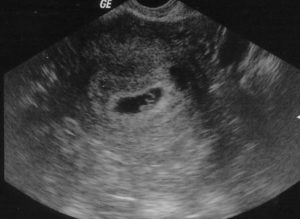

Расшифровкой данных ультразвукового исследования должен заниматься только квалифицированный специалист. На первом УЗИ специалист определяет:

- Наличие каплевидного или округлого гипоэхогенного образования, диаметр которого составляет 0,3-0,5 см. От срока зависит и размер.

- Образование должно быть окружено тонкой оболочкой. Данное образование и есть плодное яйцо.

- Наличие желтого тела.

Во время первого УЗИ обнаруживаются:

- круглое или каплевидное образование с низкой эхогенностью размером 3-5 мм. Его размер определяет срок;

- тонкая оболочка вокруг развивающегося ребёнка;

- жёлтое тело – оно вырабатывает прогестерон, способствующий сохранению плода.